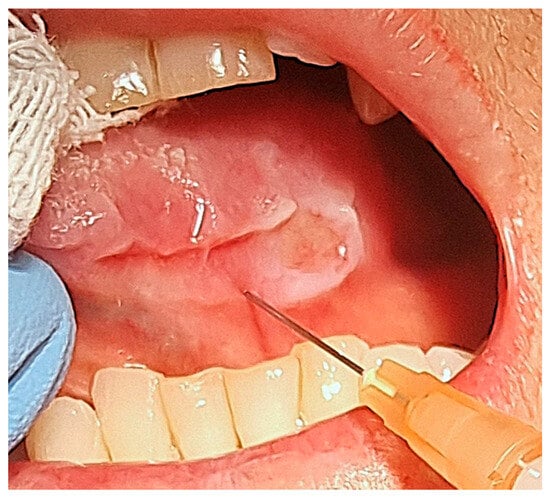

The wound was sutured with five interlocked, continuous, resorbable stitches and healed by primary intention within 3 weeks, without any complications. In the subsequent month, the residual part of the ulcer increased in dimensions (Figure 2).

Figure 2. Intraoral post-operative aspect of the ulcer after 1 month from biopsy.

After the administration of local anaesthetic without vasoconstrictor, we used sterile insulin syringes with a 30-gauge needle to slowly inject the steroid underneath the margins of the ulcer (Figure 4).

Figure 4. Intralesional injection of triamcinolone acetonide.